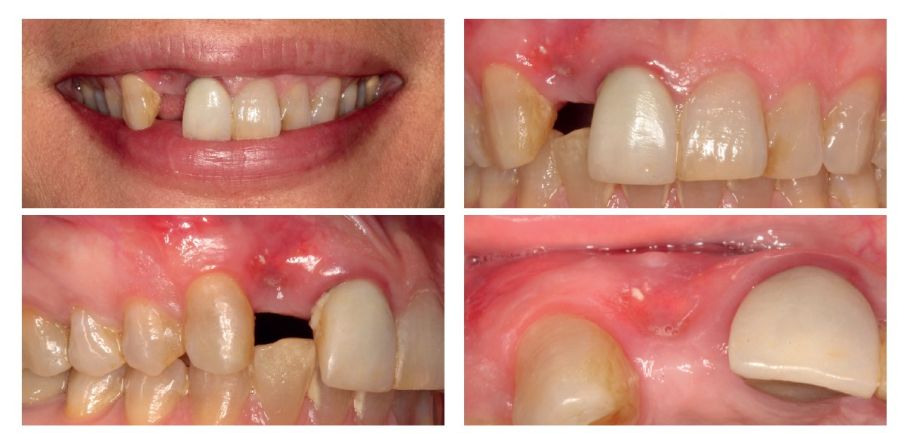

We present the case of a 36-year-old woman who comes to the clinic demanding solution for an implant located in position 1.2. This implant has carried a rehabilitation with a crown for a short period of time in which an important mucositis and loss of the thickness of the gingival tissue occurred, for which the crown was removed. The patient has a provisional removable crown and the soft tissue surrounding the area of the initial emergency of the implant-supported prosthesis is in bad condition, with a significant loss of thickness and the remains of a soft tissue fistula (Figures 1-4).